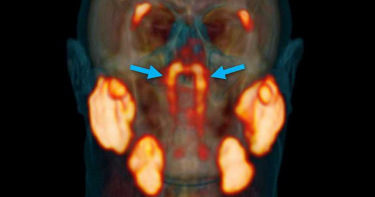

位於鼻子到咽喉的地方,最近醫生發現了新的器官,大小僅3.9公分,是在研究癌細胞時偶爾發現的。發現的單位是荷蘭癌症研究所(NCI)的沃帖爾(Wouter V. Vogel)及馬堤斯(Matthijs H. Valstar)的研究團隊,他們將平常廣泛使用在前列腺癌的「PSMA PET-CT」畫像診斷法(將顯影劑注入患者體內,而前列腺癌多半會出現含有蛋白質的谷氨酸羧肽酶,用此方式確診的診斷法。)他們發現,PSMA不只能使用在前列腺癌,對於唾腺組織也有幫助,能夠發現1千個以上眼睛無法看到唾腺或喉頭的黏膜組織,尤其集中在舌下、下顎後方及臉頰後面三處。研究團隊使用PSMAPET-CT後發現,青色箭頭所指的部分,就是新發現的唾腺組織,沃帖爾表示,人體內有3大種類的唾腺(唾腺是製造人類消化系統正常運作所需的唾液,即腮腺、頜下腺和舌下腺),黏膜上則有超過上千個人眼無法看見的小唾腺密布,這次在鼻咽頭發現相對較大的1對唾腺,非常驚訝。研究團隊此次以100人為實驗對象,使用PSMA PET-CT畫像診斷法,在所有人身上都發現此一唾腺,兩人將新發現的器官命名為「TubarialGlands(咽骨管腺)」研究團隊認為,咽骨管腺的發現,對於未來癌症治療有其重要性,咽骨管腺具有分泌唾液的作用,若用放射性治療,會損害其功能,影響患者的飲食及對話能力,沃帖爾表示,未來的研究目標,是要如何在罹癌患者選擇放射性治療後,能減少副作用的影響程度。